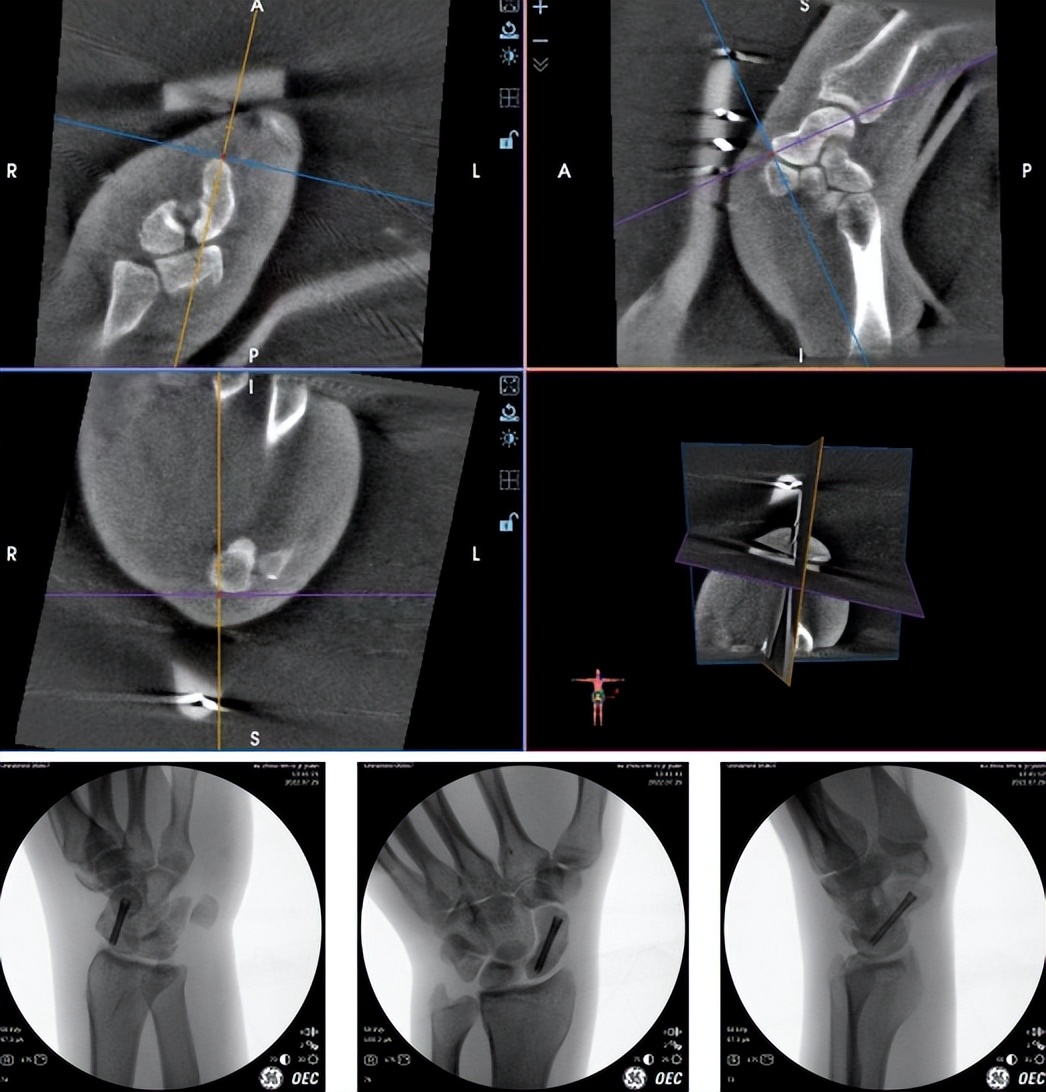

由于舟骨附近脆弱且特殊的血供系统,如果采用传统开刀手术风险较大,它不仅会破坏舟骨周围软组织的血供,且对腕关节周围韧带、关节囊均有破坏,后期瘢痕形成将影响腕关节功能,与患者及家属充分沟通后,齐伟亚主任决定使用“天玑”骨科手术机器人,完成微创手术。

齐伟亚主任手术团队当天就为王先生进行了--“天玑骨科手术机器人导航下左腕舟骨骨折复位内固定术。”术中医生先用3D“C”臂机对其进行360°环扫,随后“机器人大脑”开始成像,骨折部位得以清晰呈现。通过传送图像、规划线路等设计,将导针精准的置入术中规划的位置,主刀医生通过导针的引导,拧入一枚Herbert加压螺钉,整个手术过程仅45分钟,且手术切口不足3毫米,仅有一个钉眼大小,不仔细看根本看不到,相比较传统手术刀口长,影响美观,机器人微创手术完美的规避了这一点。

术后无需石膏外固定,王先生当天即可主动活动,术后第二天便可出院回家休养。